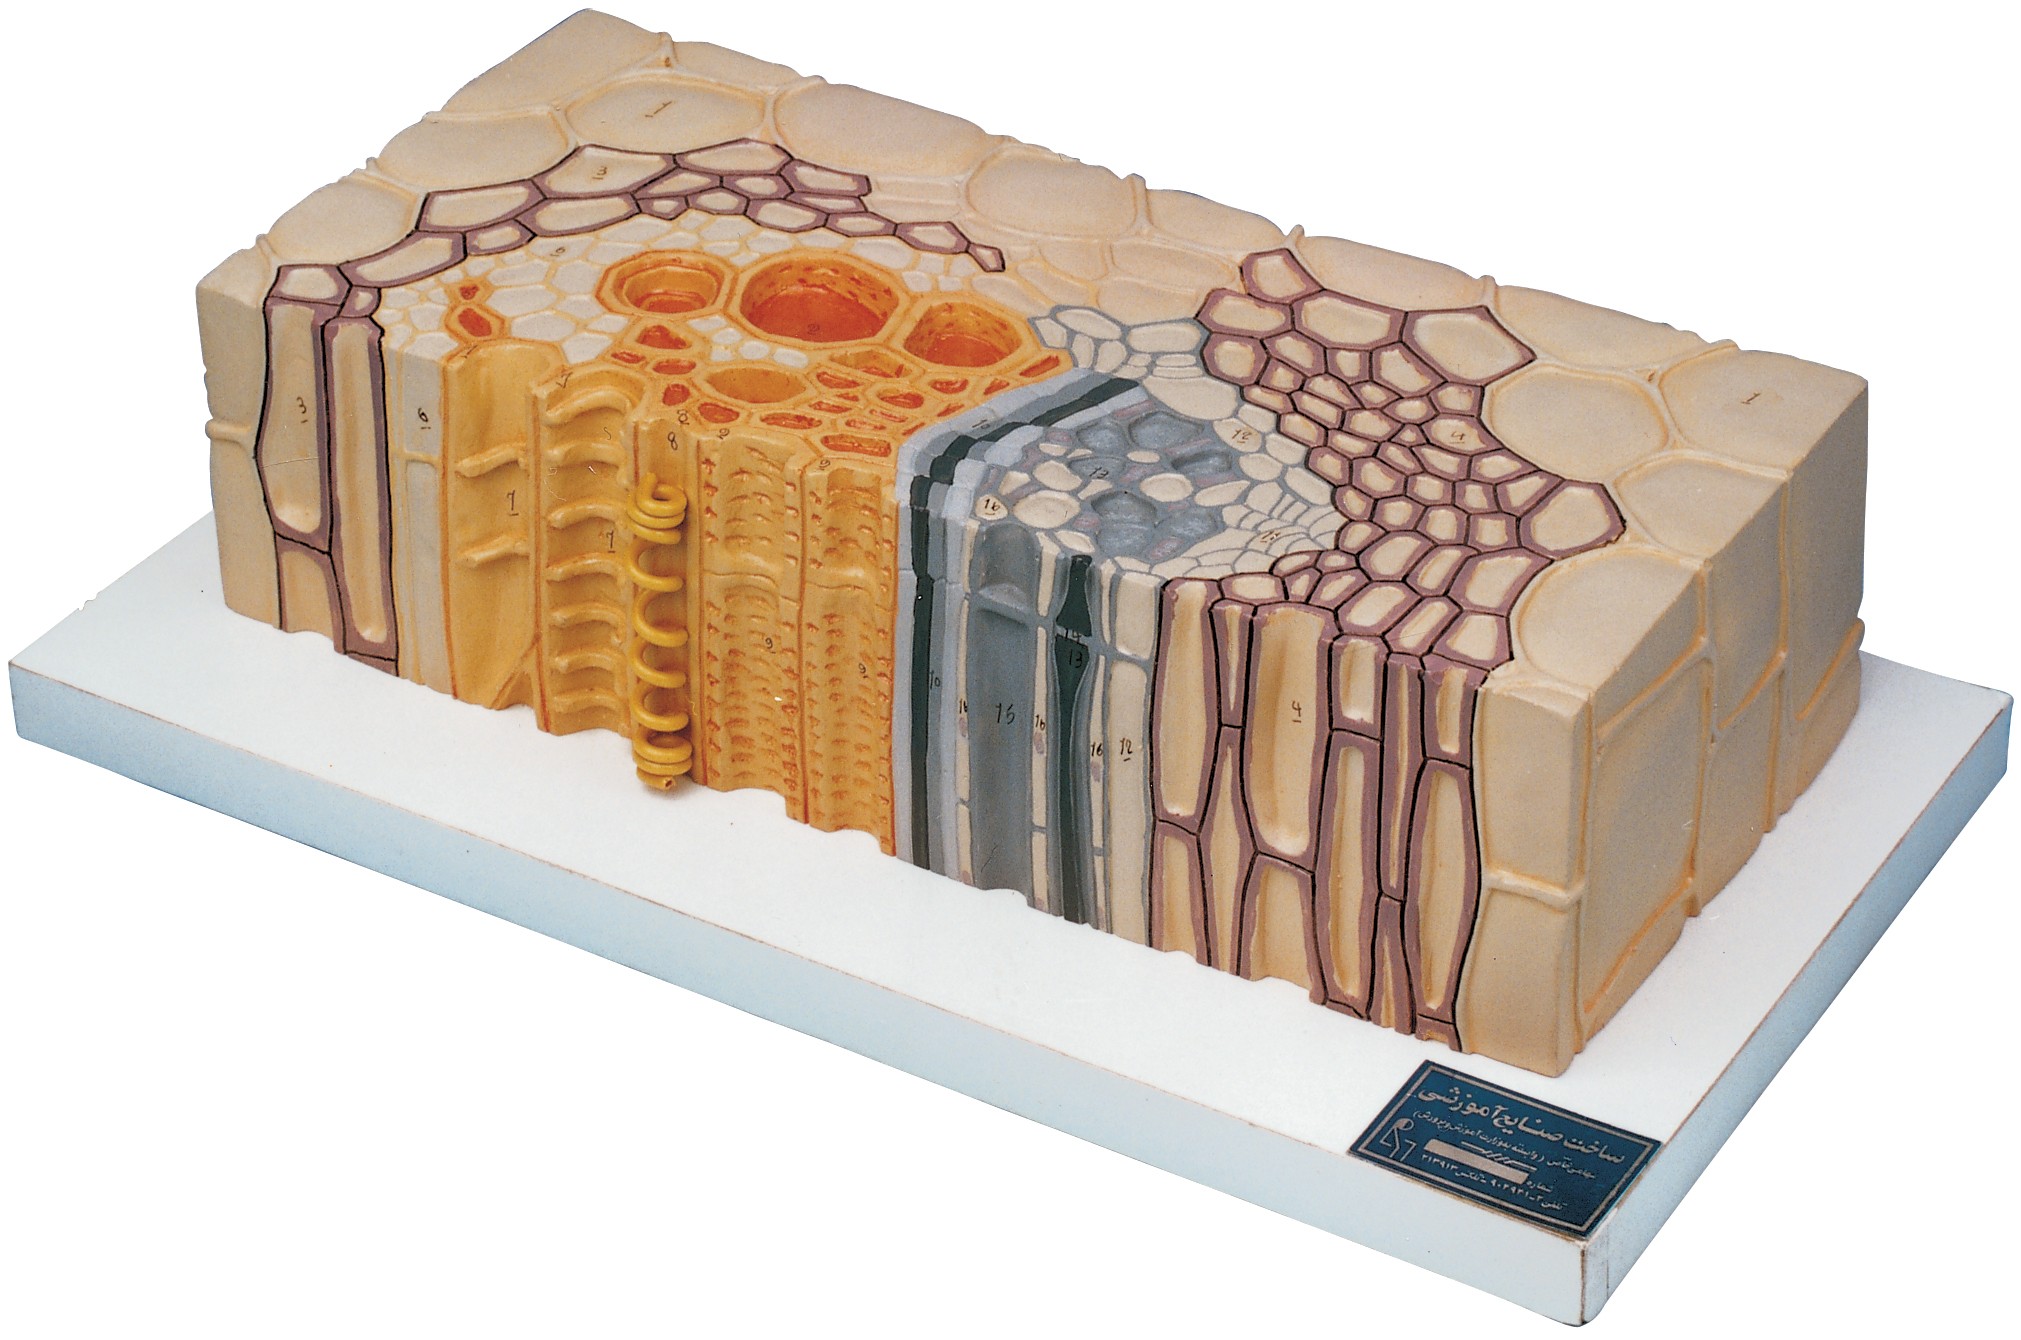

مولاژ کلمه ای فرانسوی به معنای قالب است. آناتومی بدن انسان با تجهیزاتی مانند مولاژهای پزشکی یا کالبدشناسی که نمونه هایی تخصصی و شبیه به اندام های بدن انسان هستند، به دانش آموزان و دانشجویان آموزش داده می شود. استفاده از مولاژ در روند یادگیری و آموزش تاثیر به سزایی داشته و تمامی اندام ها را با تمامی جزئیات و با کیفیت بالا می توان مشاهده و بررسی کرد. مولاژها عموما از جنس PVC نشکن، لاستیک یا فوم ساخته شده و دارای رنگ طبیعی و قابل شست و شو هستند. برخی از انواع مولاژها مناسب برای آموزش مراقبت های پزشکی و پرستاری است و امکان تمرین بانداژ، تزریق، CPR، جراحی و... وجود دارد. مولاژها معمولا هر کدام عضوی از بدن را نمایش می دهند و قابلیت تفکیک و مشاهده همه بخش های آن وجود دارد.

مولاژها معمولا با توجه به نوع اعضا و یا دستگاه های بدن در اندازه طبیعی، کوچکتر و یا چندین برابر بزرگتر ساخته می شوند تا امکان مشاهده دقیق اجزای آن ها فراهم شود. برخی مولاژها از چندین قطعه ساخته شده اند که قابلیت تفکیک دارند. علاوه بر نمایش ساختار و نحوه عملکرد اعضای بدن، ماهیچه ها و عضلات بدن را نیز می توان به کمک مولاژها مشاهده کرد.